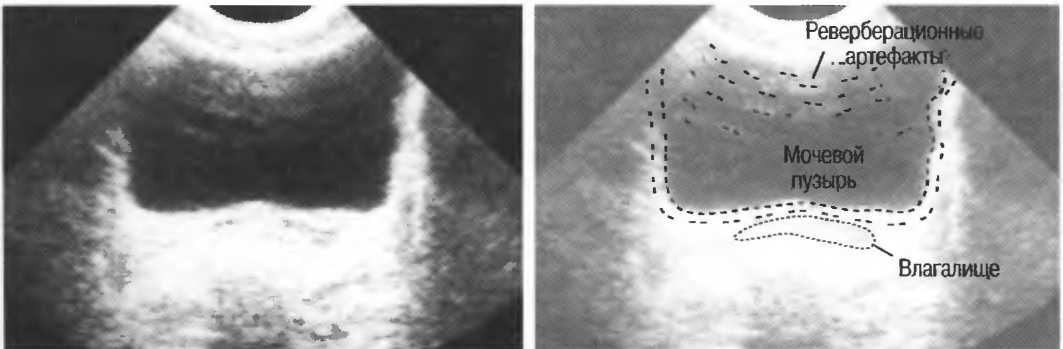

Реверберации могут полностью менять изображение, создавая линейные структуры или зеркальное отображение. Например, реверберации между параллельными слоями подкожных тканей создают параллельные линейные структуры в мочевом пузыре (рис. 20в).

Рис.20в. При сканировании матки через наполненный мочевой пузырь параллельные датчику слои тканей передней брюшной стенки могут вызывать появление ревербераций, которые определяются как зхоструктуры в передних отделах мочевого пузыря на фоне анэхогенной полости. Поперечный срез (слева) отличается от продольного среза (справа) при изменении положения датчика.